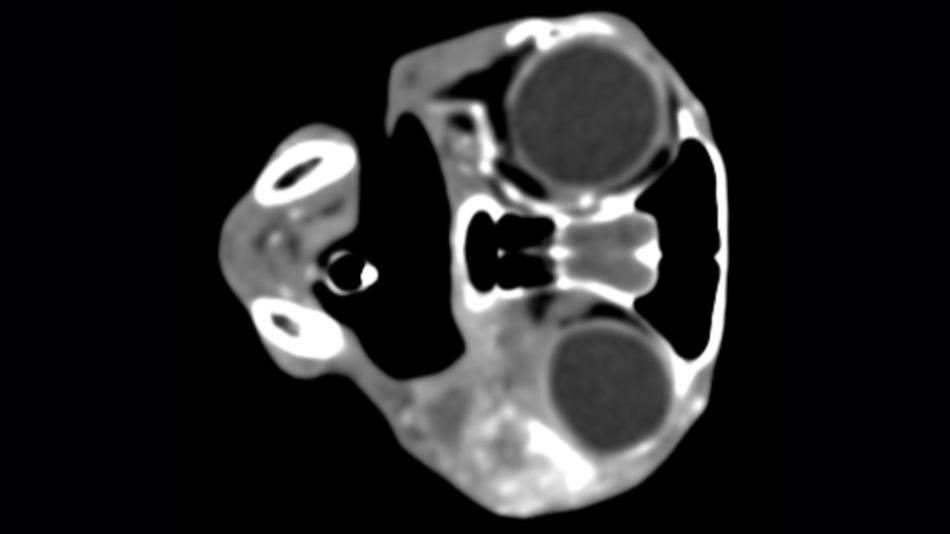

- 19:15 Uhr: Computer- und Magnetresonanztomographie des Mittelohrs bei Hunden und Katzen

2. Bereich Computertomographie und Magnetresonanztomographie

Besucherinnen und Besucher sind zur Besichtigung herzlich eingeladen. Wir erklären die Technik und wie Untersuchungen ablaufen und beantworten Fragen.